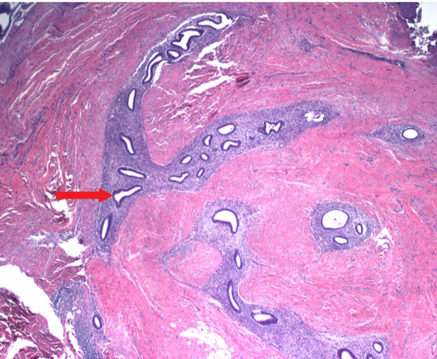

Granulosa Tumor

The granulosa cells are small and cuboidal in shape, grow in cords or sheets, and form follicle- or rosette-like structures (Call-Exner bodies) that have a gland-like appearance with a pink eosinophilic center and coffee bean nuclei (black arrows). Theca cells are plump with lipid contents, which give the mass a yellow color on gross inspection.